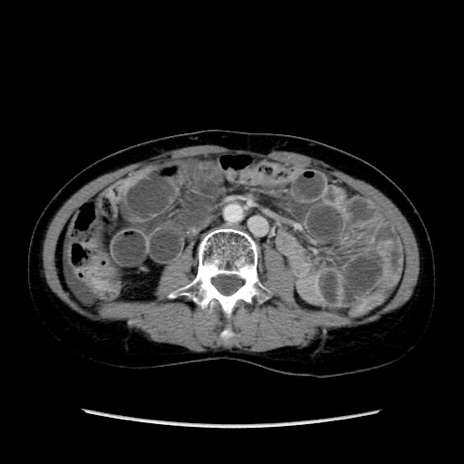

矢状断像

【症例】40歳代 女性

【主訴】上腹部痛、嘔気・嘔吐

【現病歴】約9時間前頃から急に上腹部痛、嘔気、嘔吐が出現。改善しないため救急要請。

【既往歴】子宮頚癌(広汎子宮全摘術、放射線療法)、腸閉塞

【身体所見】腹部:平坦、軟、腸雑音亢進、上腹部を中心に腹部全体に圧痛あり。

【データ】WBC 8400、CRP 0.03